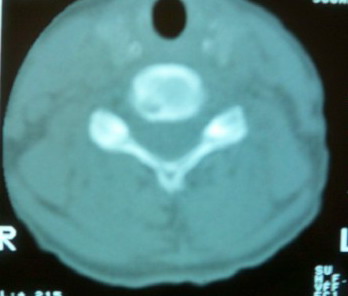

女。70 主因 头晕

颈椎周围软组织无明显变化,颈椎右后缘见低密度影,外周见硬化带,考虑许莫氏结节。

周围硬化,但不是很厚,考虑1骨纤2嗜酸性肉芽肿3许莫氏结节。

颈椎右后缘见低密度影,无明显分隔,外周见硬化带,周围软组织未见异常,考虑许莫氏结节。